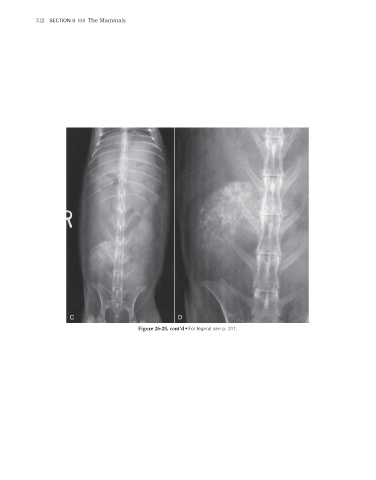

Figure 26-25, cont’d • For legend see p. 311.